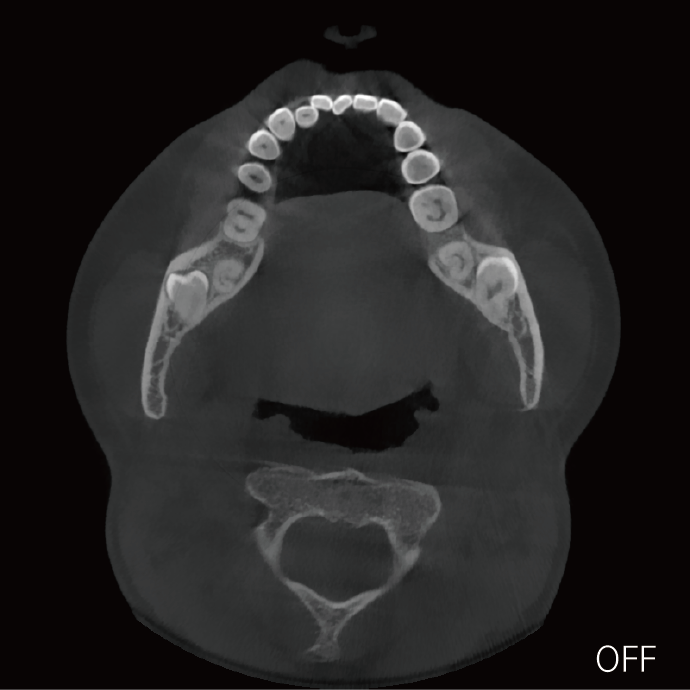

临床样片